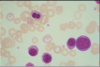

A

blast

22

Q